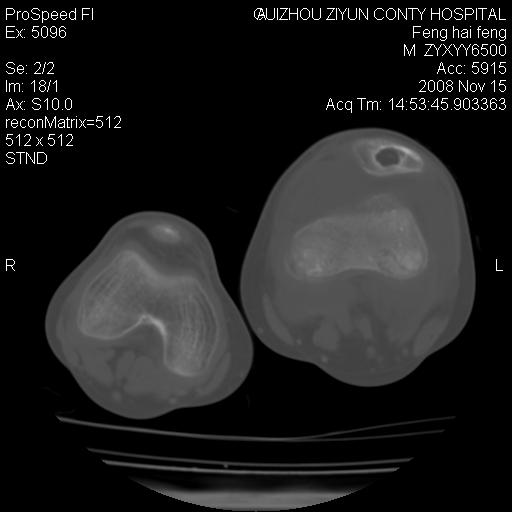

标题: CT16656:M 14Y 左膝关节肿胀一年余。其余病史不详。 [打印本页]

标题: CT16656:M 14Y 左膝关节肿胀一年余。其余病史不详。

考虑左侧髌骨结核;左膝关节滑膜肿胀、增厚,关节囊积液。

左膝滑膜型关节结核可能性大!支持!滑膜型关节结核主要ct表现:关节囊肿胀,积液,关节面见小破坏灶,并见点状死骨!

好大的左腿!考虑左侧髌骨结核,左膝关节滑膜肿胀、增厚,关节囊积液。

左侧髌骨结核;左膝关节滑膜肿胀、增厚,关节囊积液